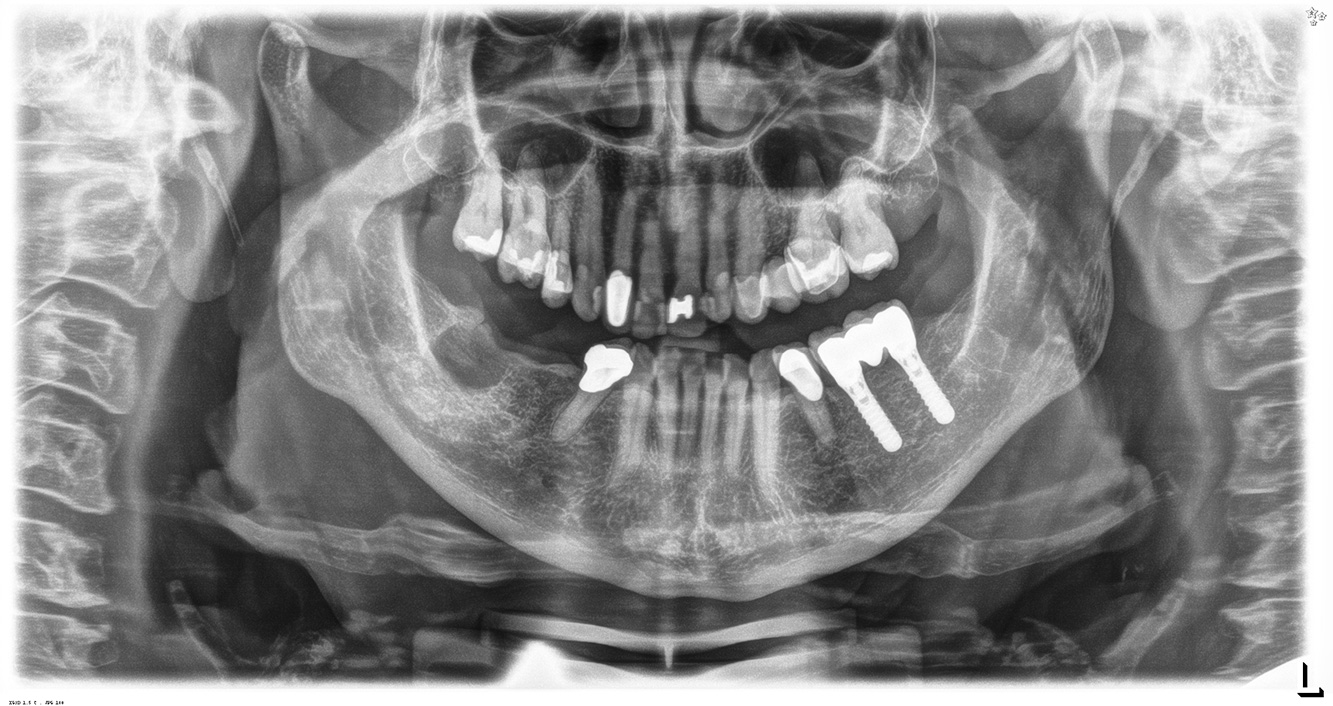

The (orally) healthy patient with implants

In the medical history, the 55-year-old patient states that he has no systemic disease and is not taking any medication. The patient’s lifestyle is similarly unremarkable. The patient has a few tooth restorations and two implants (2nd and 4th quadrants). On the basis of current findings, gingivitis is identified in an otherwise stable periodontal condition on the reduced periodontium (stage III, grade A). more

The healthy patient with pre-existing periodontal disease & peri-implantitis

A 52-year-old patient presents at a preventive care session. The patient has no systemic disease and is not taking any medication. He has had various dental treatments and also has two active carious lesions. In addition, the patient has four implants (2nd, 3rd and 4th quadrants). He is revealed to have early periodontal disease (stage IV, grade B). His periodontal condition is stable; a probing depth of Probing depths (ST) of 5 mm is only evident at the implant in region 36. Gingivitis is also identified. more

The healthy patient with early periodontal disease

The 68-year-old patient has no general health conditions and is not taking any medication that may be relevant to her oral health, and her lifestyle does not pose any particular risk. The patient has two dental implants (3rd quadrant, for five years) and a previous case of periodontal disease (stage IV, grade B periodontitis) with tooth loss. Currently the periodontal conditions are stable. However, periodontitis significantly increases the biological complications of implantations and there is a risk of implant loss (21). Four recommendations can be determined for the prophylaxis session. more